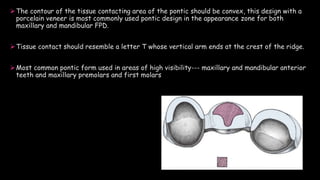

The document discusses pontic design for fixed dental prostheses. It covers pretreatment assessment of residual ridge contours, classifications of ridge deformities, surgical modification techniques, and ideal requirements for pontics. Pontic designs are classified based on their shape and materials. Factors in pontic selection include esthetics and oral hygiene. Common designs for anterior and posterior regions are described, including sanitary, ovate, and saddle pontics. Biological considerations for pontic design involve maintaining the residual ridge, abutment teeth, and supporting tissues.